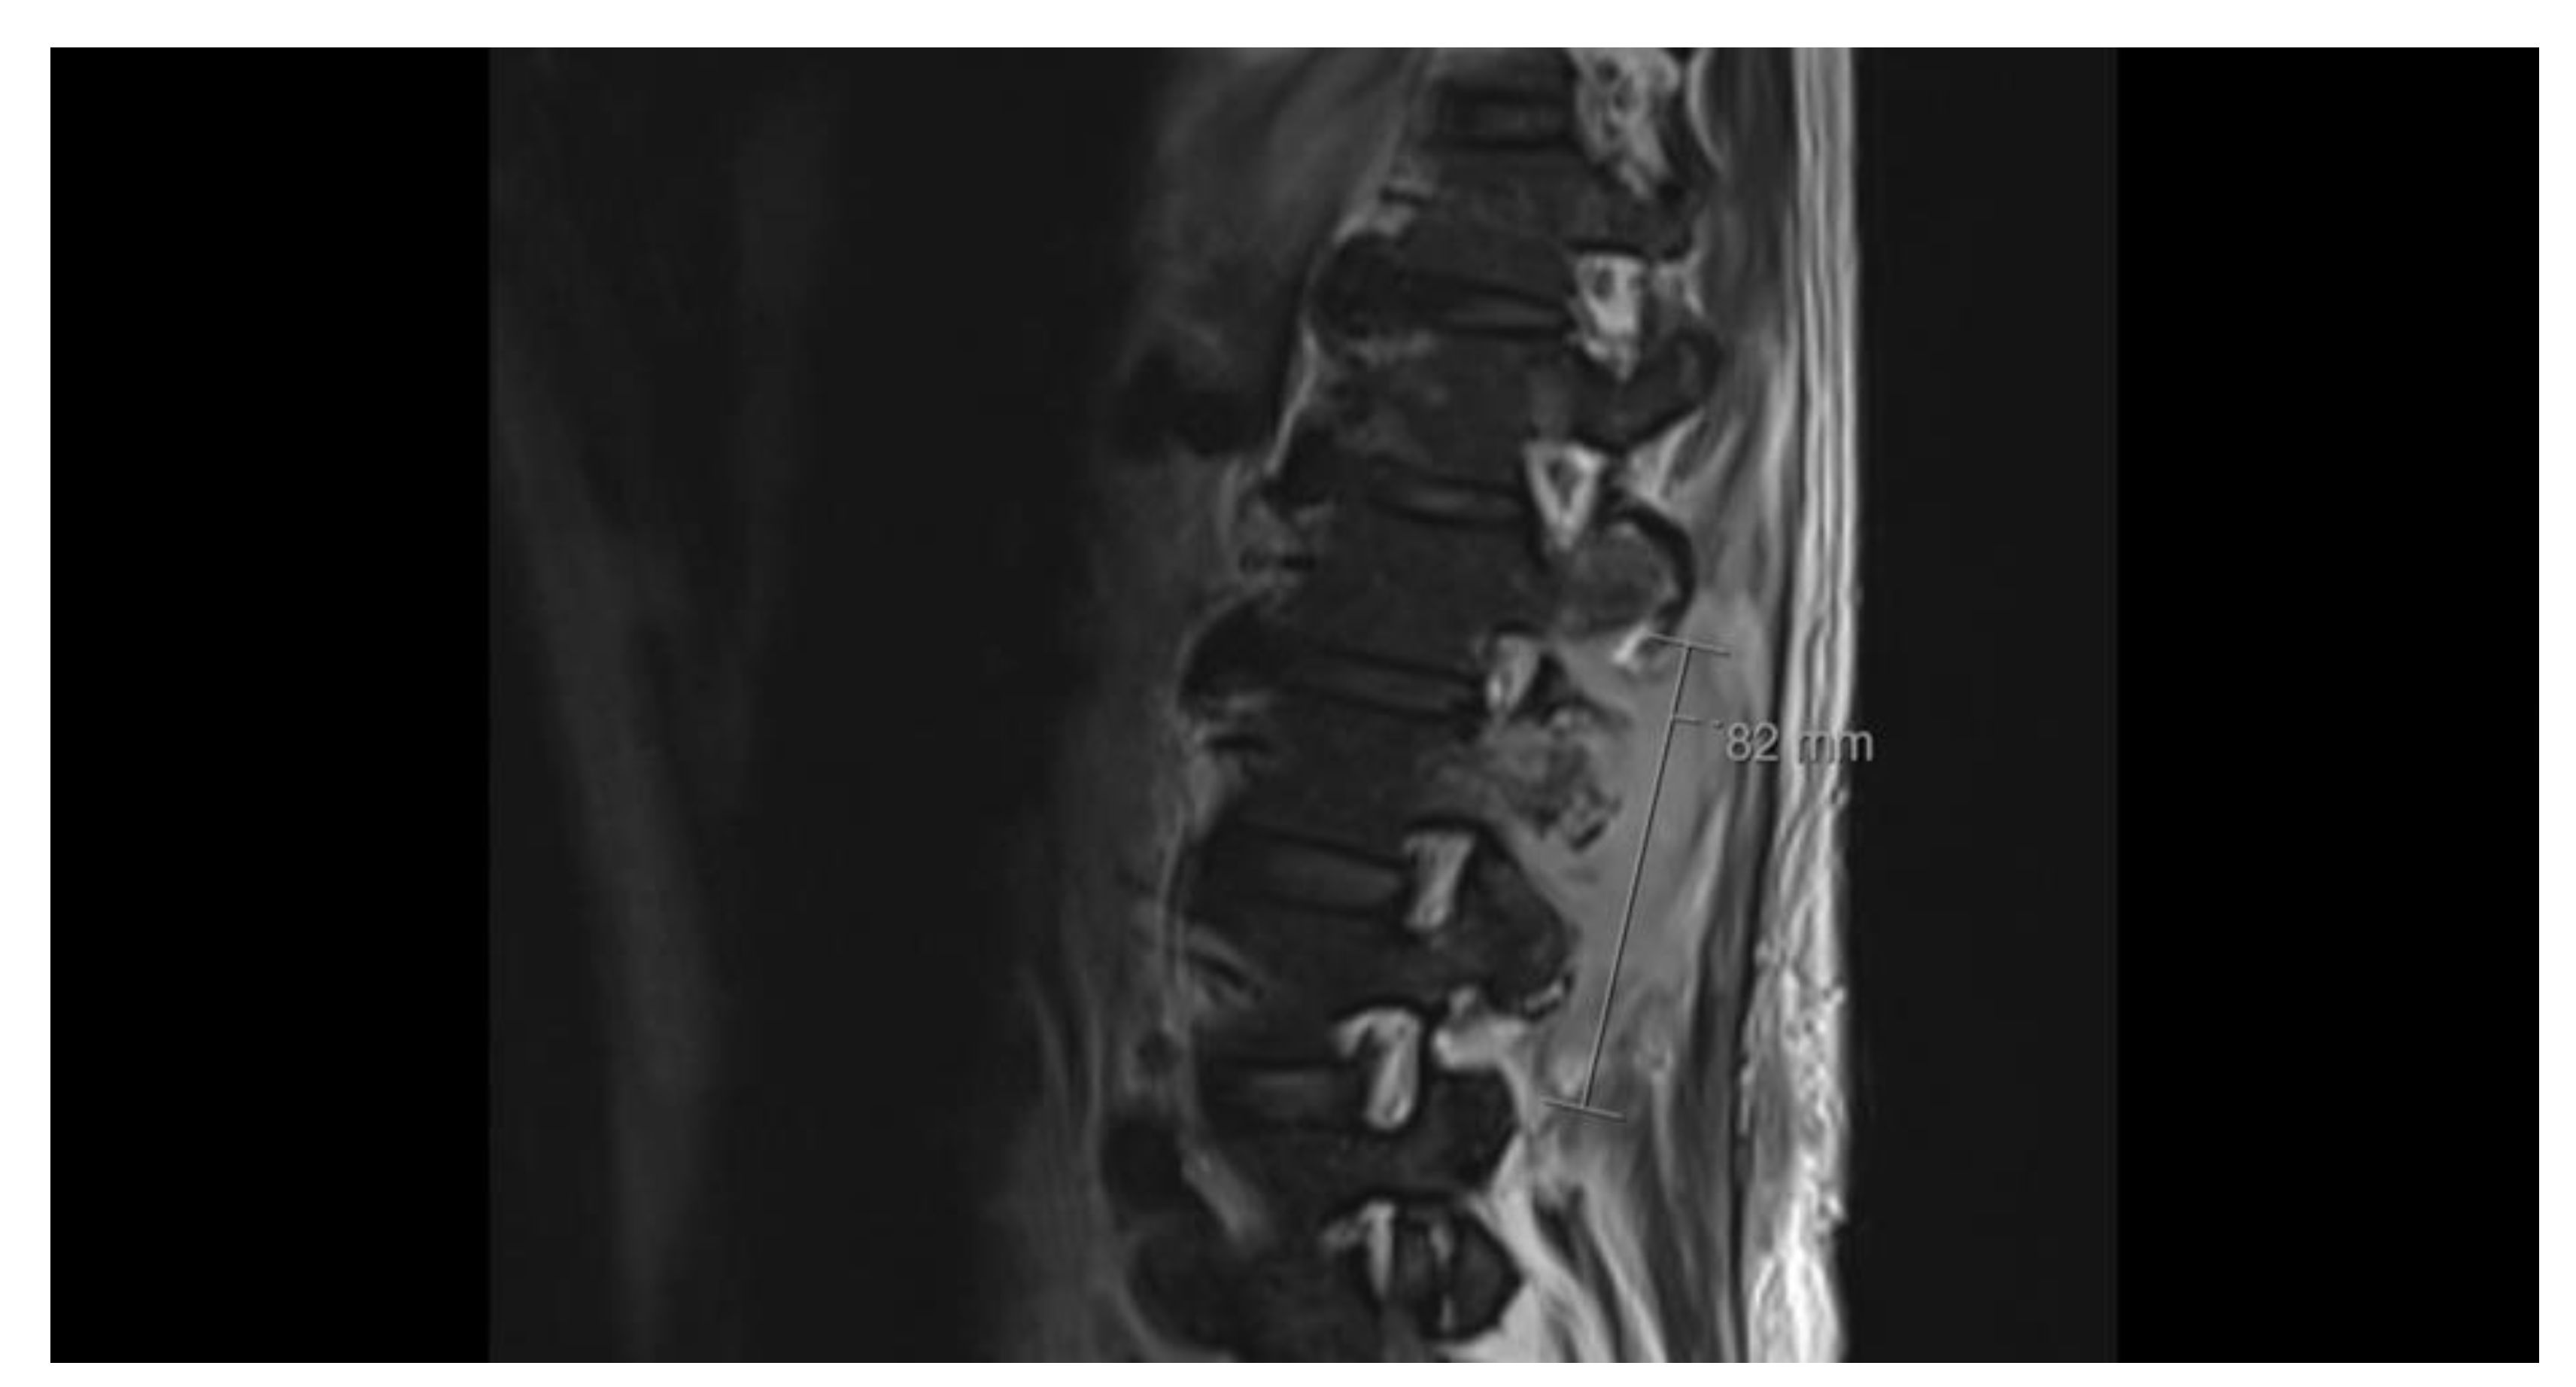

Upon re-admission for persistent symptoms in his second hospitalization, the patient’s vitals were: blood pressure of 170/92 mmHg, heart rate of 79 beats/min, and temperature of 36.7 °C. Lab workup was notable for a lactic acid of 1.7 mmol/L (normal: 0.4 – 2.0 mmol/L), white blood cell count of 6.0 x 10E9/L (normal: 4.0 - 11 x 10E9/L), a procalcitonin of 0.10 ng/mL (normal: < 0.05 ng/mL), a CT head revealed 9 mm enhancing supratentorial lesions (Image 1: Supratentorial Lesions on CT Head), and a repeat MRI of the lumbar spine demonstrated concerns for a neoplastic process from the spinous process of L2 (Image 2: Concerns of Neoplastic Processes on Spinal MRI). The reviewing radiologist favored lymphoma with additional involvement of the bilateral inferior articular process. Neurosurgery consultation deemed no significant interventions for his cranial lesions necessary. However, the patient underwent an IR-guided biopsy of the spinal lesion, ultimately yielding only granulation tissue without evidence of malignancy. Given his housing instability, the patient’s final antibiotic regimen based on susceptibility and feasibility entailed oral levofloxacin, oral linezolid, and oral trimethoprim-sulfamethoxazole (Table 1: Susceptibility Pattern of Nocardia Transvalensis).

Figure 1. Supratentorial Lesions on CT Head.